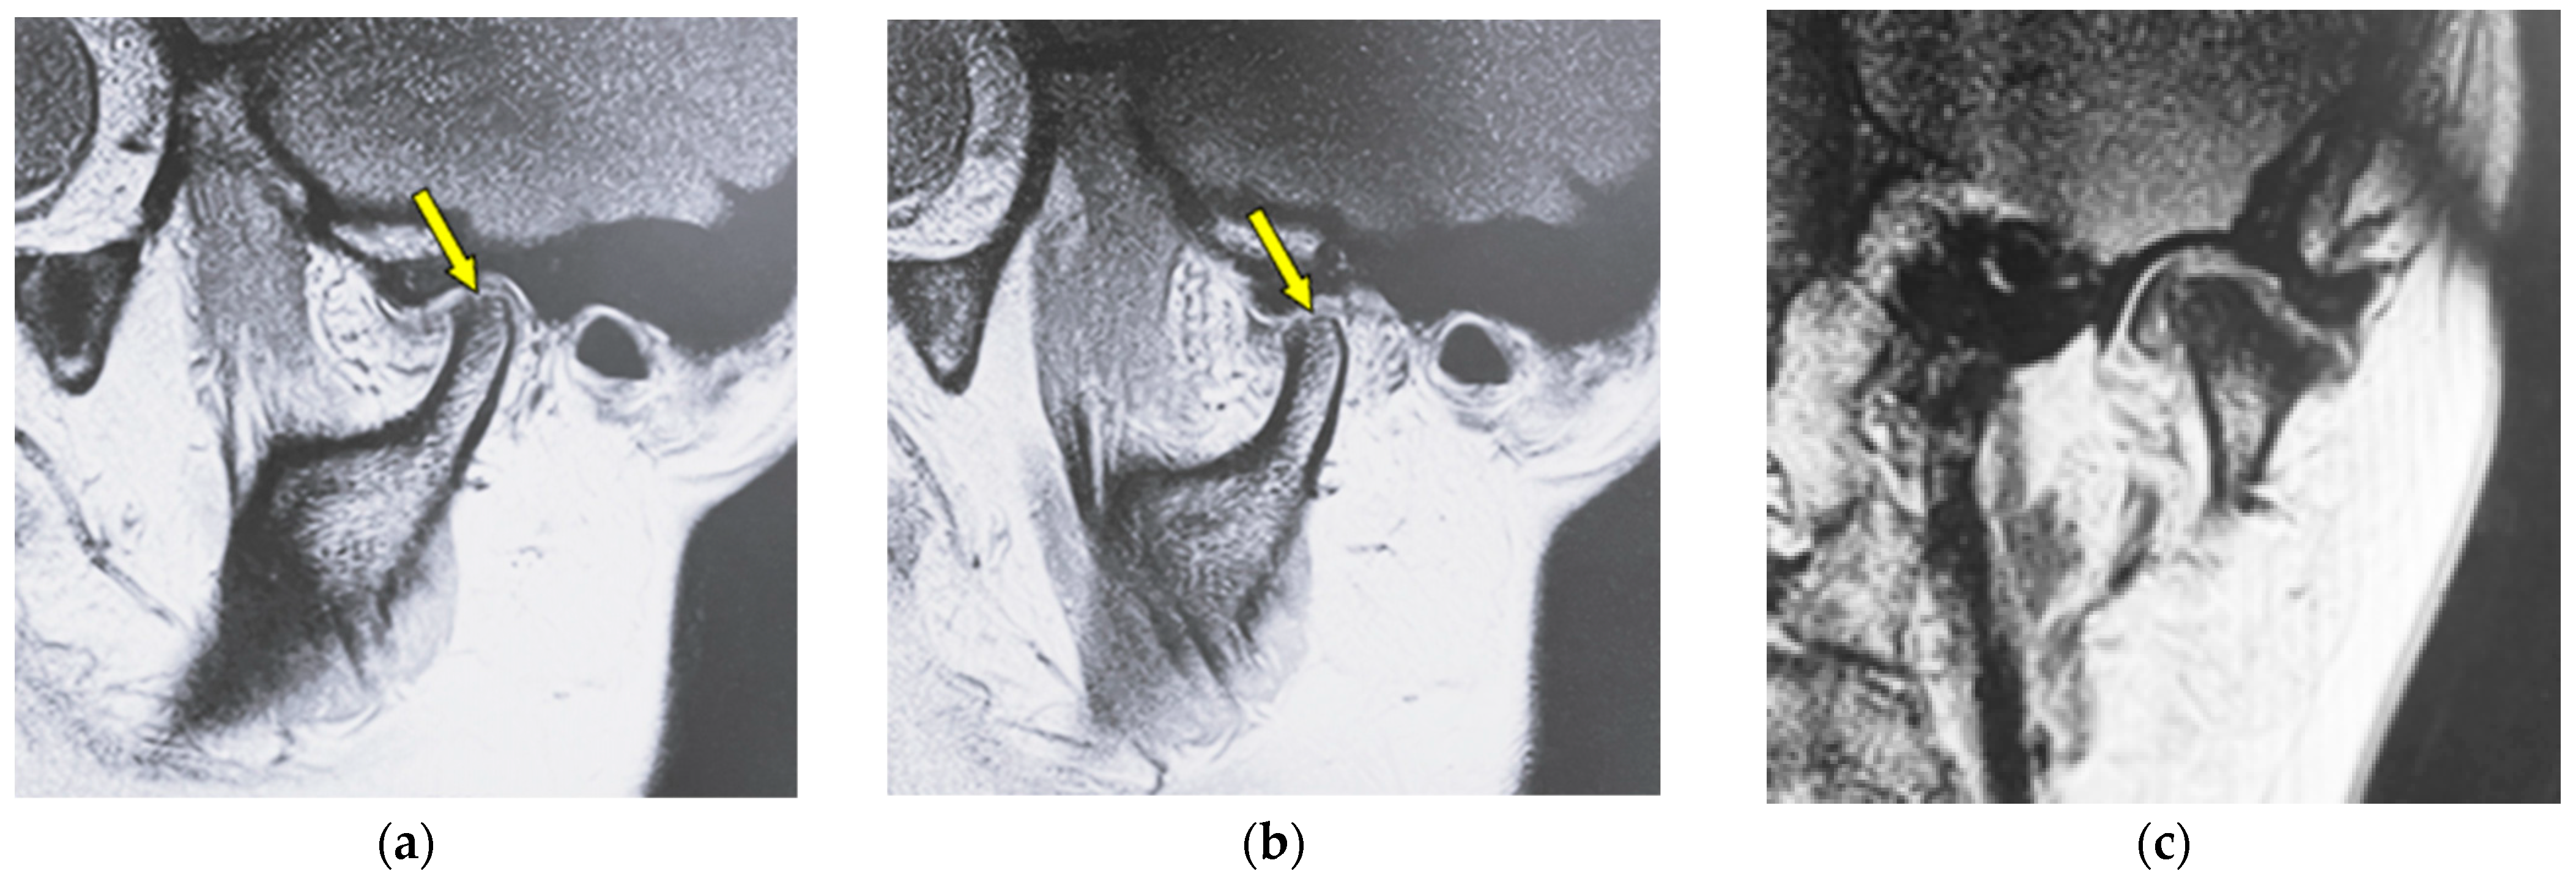

Figure 1 shows MR images of a 43-year-old woman with erosion (left TMJ). Sagittal oblique cross-section imaging (proton-density-weighted) shows anterior disc displacement at the mouth-closing position (Figure 1a) and at mouth-opening positions (Figure 1b).

MR image (proton-density-weighted) of a 43-year-old woman (disc displacement without reduction, left disc): (a) sagittal oblique cross-section imaging in the mouth-closing position; (b) sagittal oblique cross-section imaging in the mouth-opening position; (c) coronal oblique cross-section imaging in the mouth-closing position. The arrow shows the part with erosion.